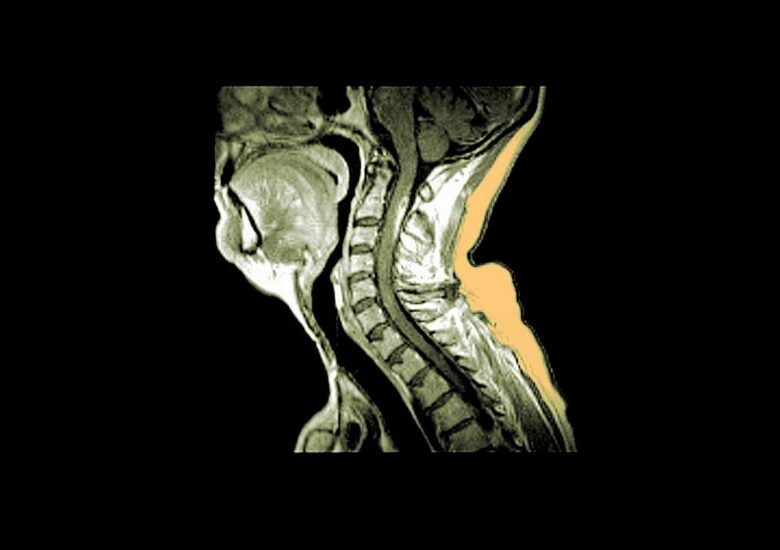

Când scleroza multiplă atacă măduva spinării

Leziunile măduvei spinării sunt mai frecvent observate în formele progresive de scleroză multiplă și pot duce la un risc crescut de dizabilitate. Aproape toți cei care suferă de scleroză multiplă